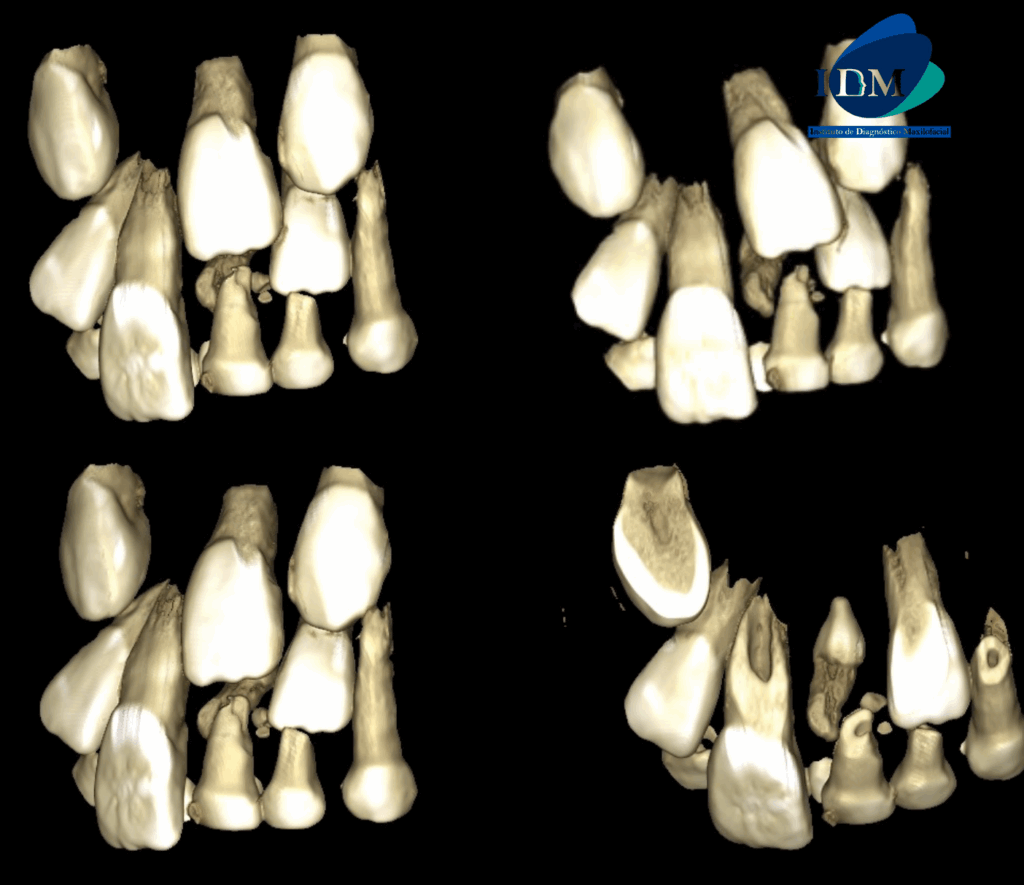

En las reconstrucciones 3D se representa de manera didáctica Odontoma Compuesto y Mesiodent (Figura 4).

RECONSTRUCCIÓN 3D